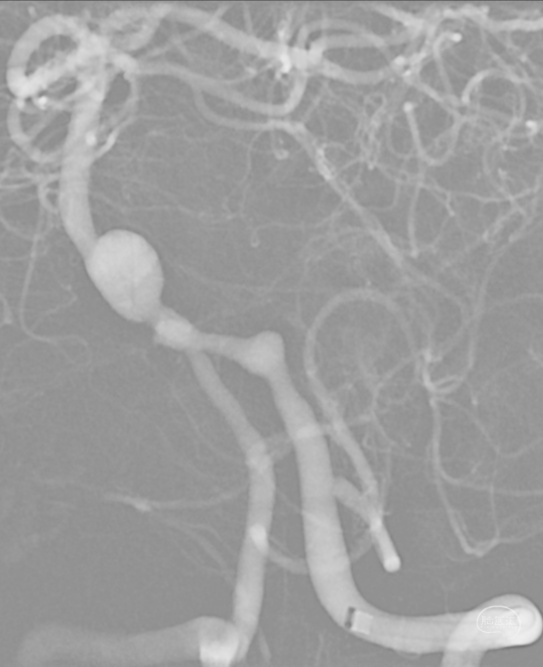

3D重建显示基底动脉下部、双椎结合部、左椎多发夹层动脉瘤:

辅助检查:头颅CTA(外院)检查提示:椎基底动脉多发动脉瘤。